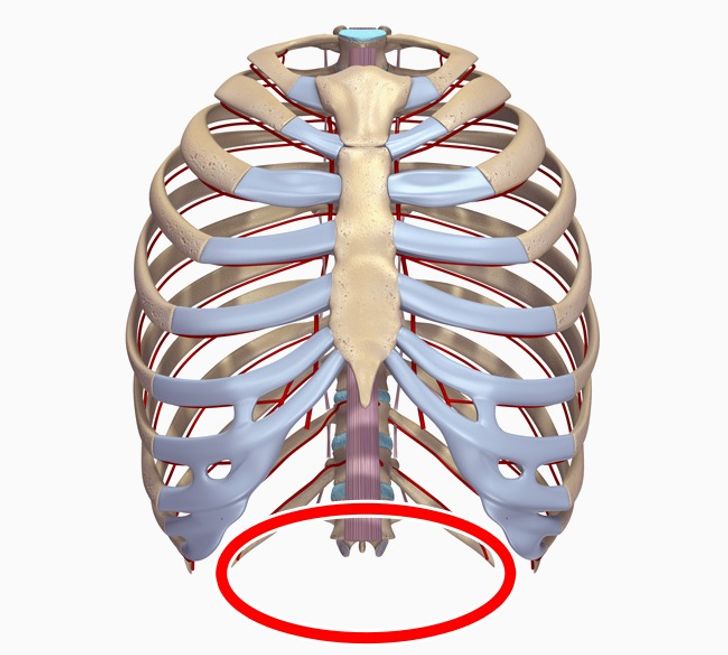

8. Trzynaste żebro

Nasi najbliżsi kuzyni, szympansy i goryle, mają dodatkowy zestaw żeber. Większość ludzi natomiast ma ich 12 – jedynie 8% dorosłych ma jeszcze jedno dodatkowe.